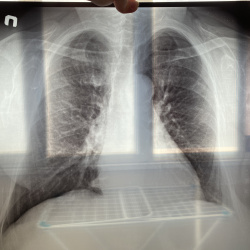

Пожалуйста посмотрите рентген лёгких

Расшифруйте пожалуйста снимок лёгких моей бабушки. Ей 72 года.

С учетом качества изображений - в пределах возрастных изменений (диффузный пневмосклероз, атреросклероз аорты,дегенеративные изменения позвоночника. Ничего более серьёзного не найдено.